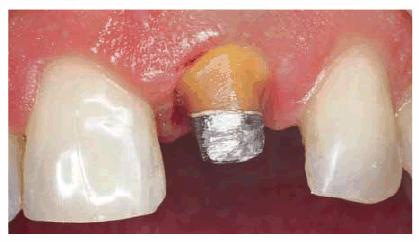

concept is supported by most studies. Such a patient can be seen in Figur 323s1823d es 18-10A 18-10B to G, and 18-10H. Post restorations used in anterior

Figur 323s1823d e 18-10A: This young lady fractured her left central and lateral incisors in an accident. Because the original teeth had protruded before fracturing, the patient requested that the restoration be accomplished with an improved appearance in the most permanent treatment available.

Figur 323s1823d e 18-10B to G: Following endodontic therapy, two cast posts were constructed and cemented to place in the prepared incisors.

Figur 323s1823d e 18-10H: The final all-ceramic crowns were bonded to place. Note the natural result of both the shade and texture of the crowned teeth.